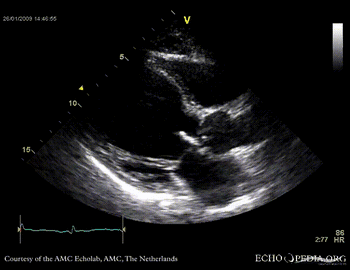

Aortic valve endocarditis with vegetation

Case description: This patient had endocarditis with an aortic valve vegetation

E00117.gif E00119.gif

PLAX aortic valve vegetation A3CH aortic valve vegetation